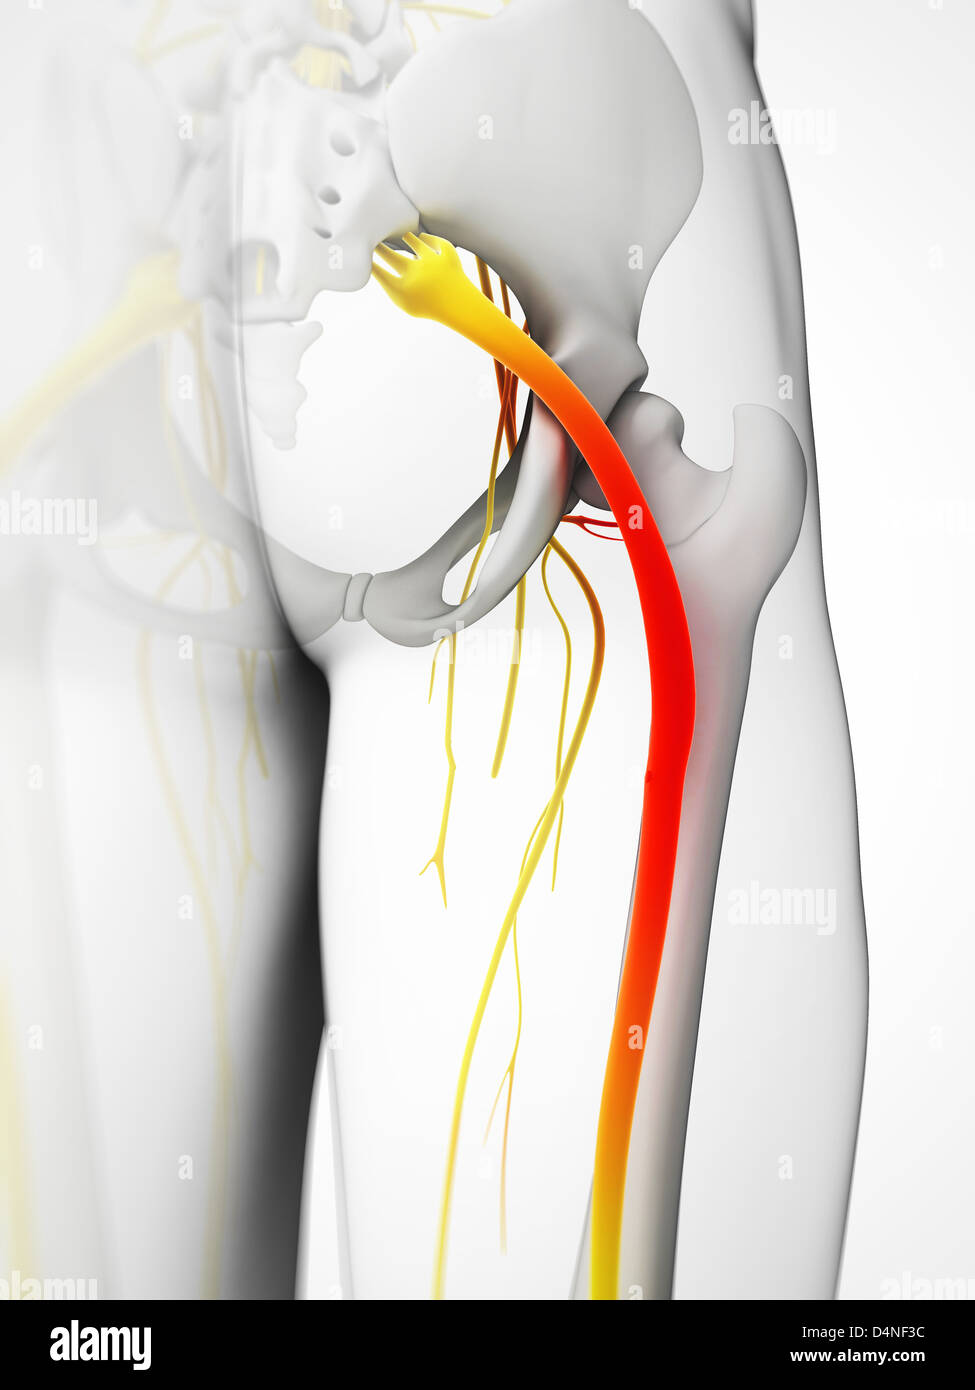

Nerf sciatique Banque D'Imageshttps://www.alamyimages.fr/image-license-details/?v=1https://www.alamyimages.fr/photo-image-nerf-sciatique-54562576.html

Nerf sciatique Banque D'Imageshttps://www.alamyimages.fr/image-license-details/?v=1https://www.alamyimages.fr/photo-image-nerf-sciatique-54562576.htmlRFD4NF3C–Nerf sciatique